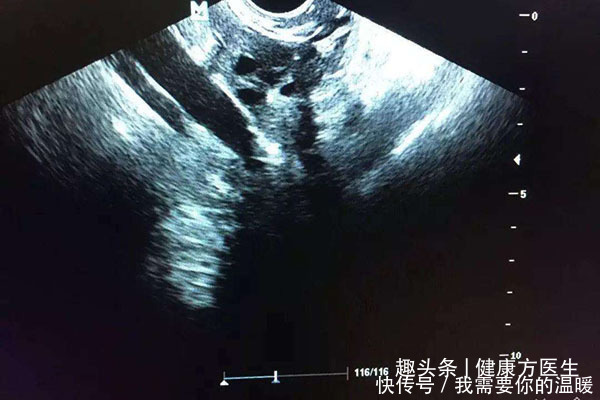

- 卵巢早衰|30岁女白领连续几个月不来月经,丈夫陪其去医院,回来就要离婚